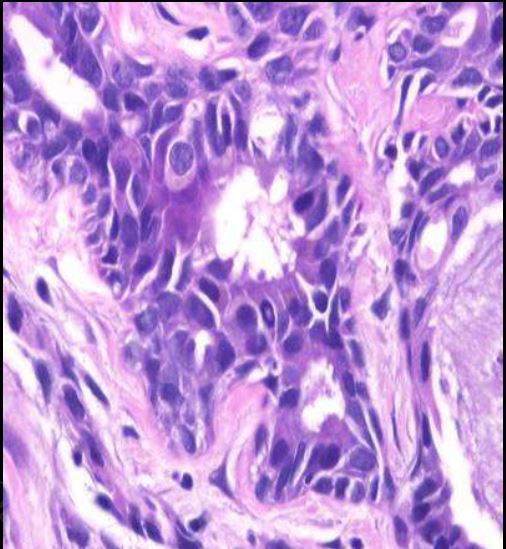

BQ SLIDE! Name this thyroid cancer.

Insular carcinoma